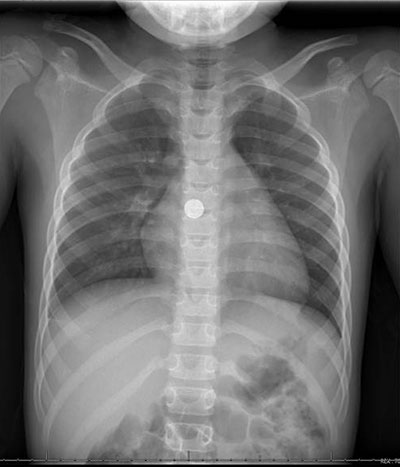

"A swallowed button battery, if stuck in the esophagus, is a true emergency and can cause life-threatening complications,” Dr. Barth says. “It is impossible to tell if the battery has passed into the stomach without an x-ray, so even if the child looks fine after swallowing it, the family must seek medical care immediately."

If the swallowed object is not a button battery or multiple magnets, and your child does not display any symptoms, your doctor may prescribe a "wait and see" approach and monitor the object's progress using X-rays or other imaging tests. Foreign objects usually take about one to two weeks to pass through the system. If the object is not out by four weeks, your child's doctor may refer you to a pediatric gastroenterologist for further evaluation. Depending on the item's location, endoscopic removal may be recommended.